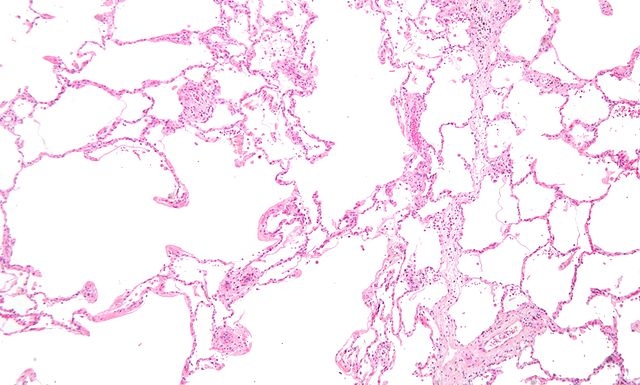

A prevalência e severidade das alergias e, em particular, da asma estão aumentando no mundo todo (imagem: Wikimedia Commons)

De acordo com Momtchilo Russo, pesquisador responsável pelo projeto temático, a prevalência e severidade das alergias e, em particular, da asma estão aumentando no mundo todo.